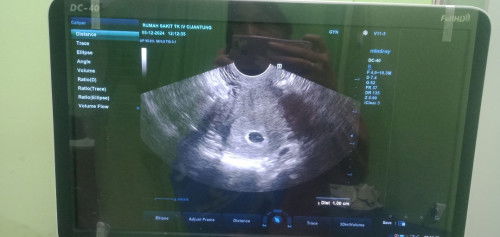

Semalem keluar flek coklat sedikit sampai hari ini masih flek tapi keluar nya sedikit bgt , akhirnya mutusin buat usg kata dokter sih gpp aman aman aja cuma rasa takut dan khawatir aku sendiri berlebih karena sebelumnya pernah keguguran, dokter saran untuk balik lagi 2minggu USG ulang Saran dong Bun harus minum obat penguat kandungan atau gimana ya? Aku panik + takut campur aduk😭#Sharing_dong_Bund #bantujawab #SeriusTanya #firstmom